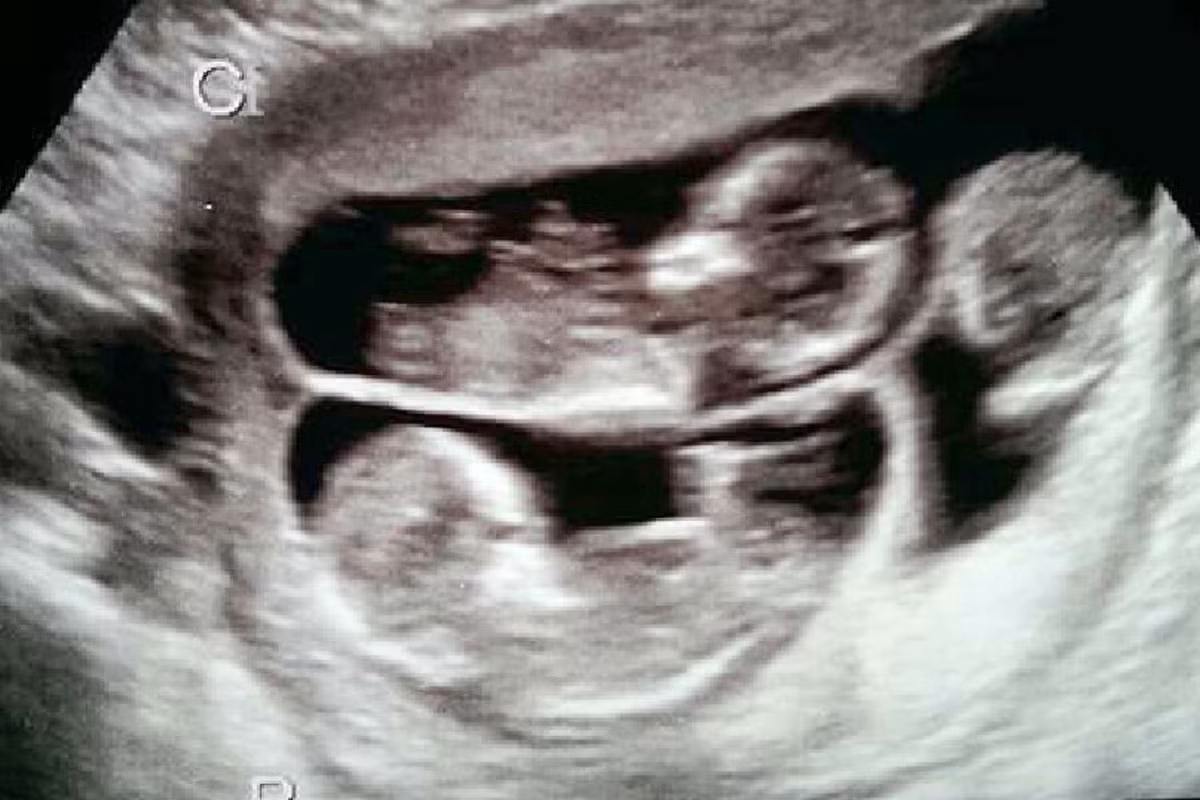

Khi siêu âm có 3 nhịp tim bà Sharon đã khóc vì vui sướng. Ngày 21 vừa qua, 3 em bé kháu khỉnh đã chào đời.